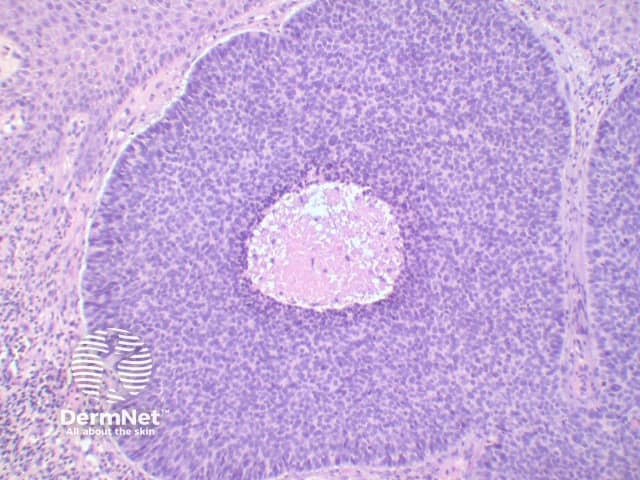

The key feature of basal cell carcinoma at low power magnification is of a basaloid epithelial tumour arising from the epidermis (figure 1). The basaloid epithelium typically forms a palisade with a cleft forming from the adjacent tumour stroma (figure 2). Centrally the nuclei become crowded with scattered mitotic figures and necrotic bodies evident (figure 3). A useful distinguishing feature from other basaloid cutaneous tumours is the presence of a mucinous stroma (figure 4). Some tumours may also show foci of regression, seen as areas of eosinophilic stroma with lack of basaloid nests.

Figure 2